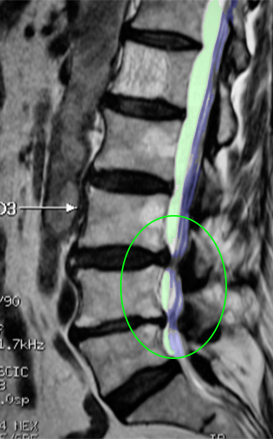

SpinalStenosis2 ForamenStenosis

Αριστερά: Στένωση οσφυϊκού σπονδυλικού σωλήνα. Δεξιά:Φυσιολογικό νευρικό τρήμα στην κορυφή (πράσινο) με ελεύθερο νεύρο στο κέντρο (μπλέ περίγραμμα). Στενό τρήμα (κυανό βέλος) και ουσιαστικά κλειστό τρήμα,το οποίο εμπεριέχει μόνο το πιεσμένο νεύρο (πράσινο βέλος). Τεμάχιο δισκοκήλης εντός του τρήματος (κόκκινο περίγραμμα).